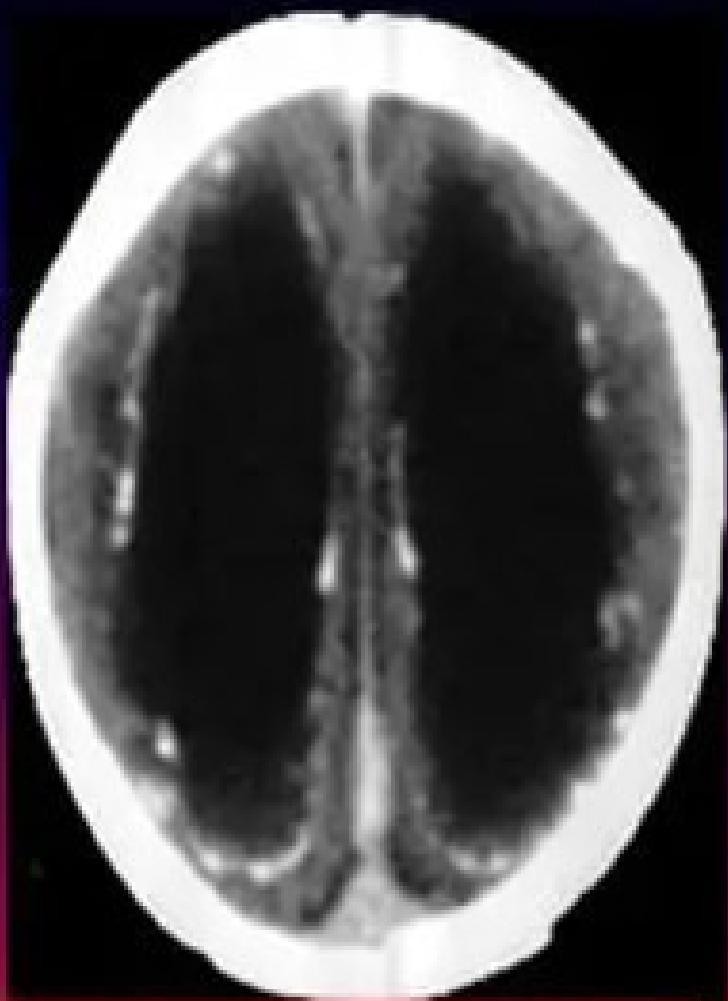

- Leads to: Inflammation, Cellular destruction, Calcification (especially in periventricular areas of the brain).

- Neurological: Microcephaly, Seizures, Intracranial calcifications (classically periventricular).

Ventriculomegaly and calcification of congenital CMV

- Imaging: Cranial ultrasound/CT → periventricular calcifications, ventriculomegaly.